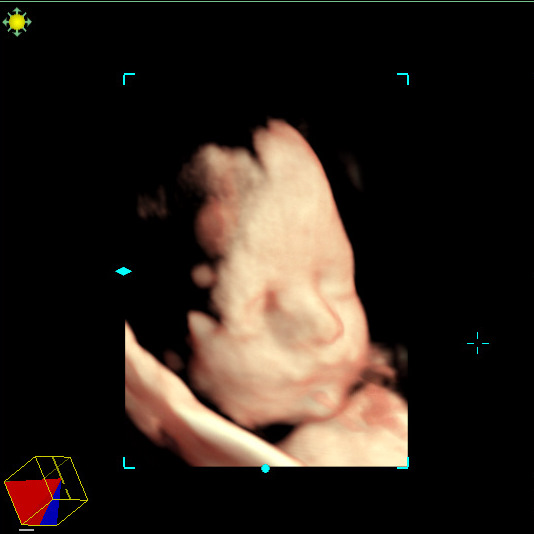

Here is what we are looking for in an image of the cervix. Must see the internal and external OS, the endocervical stripe and a symmetrical uterine wall around the internal OS. If all of these structures are not seen then you must do a transvaginal exam.